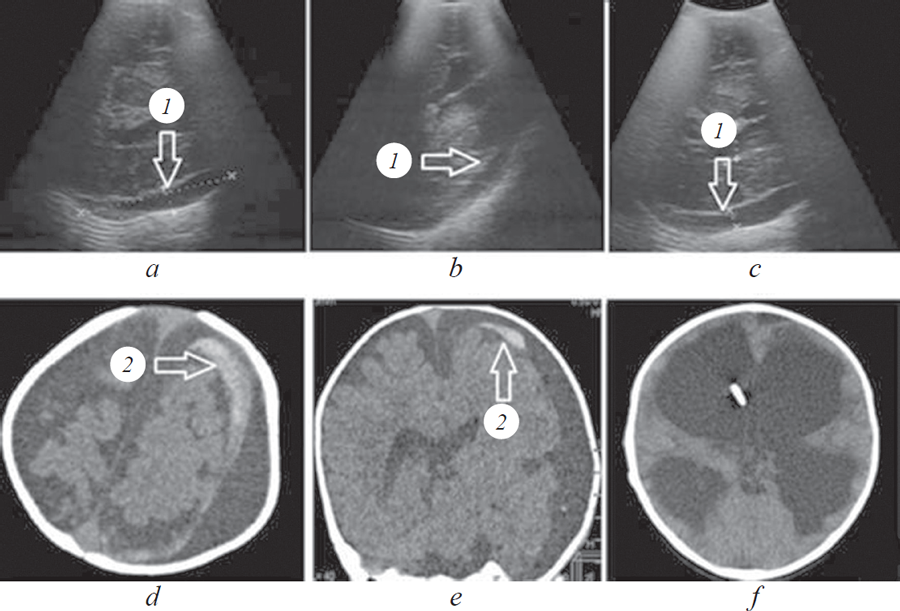

Materials and methods. Clinical and clinical-sonographic evaluations of 256 patients aged 0-18 years with clinical criteria of mild traumatic brain injury were performed. Depending of detected clinical and neurological risk factors and the results of the primary clinical and sonographic examination, children were divided into two groups: group I (high or medium risk of traumatic intracranial injury) – 174 (67.9%), group II (low/no risk of traumatic intracranial injury) – 82 (32.1%). Verification of important traumatic and non-traumatic intracranial changes revealed by primary sonographic exam was confirmed by using computerized tomography.

Results and conclusion. Identification of traumatic intracranial injures by results of primary clinical examination is most effective when two or more higher or medium risk factors were detected. Application of primary clinical and sonographic examination increases diagnostic efficiency of neurological evaluation to 10.1% and the possibility of detecting traumatic intracranial injures to 57.1%. In 7.0% of cases emergency computed tomography were determined, dynamic observation was performed in 32.1% of cases. Significant non-traumatic brain diseases (cysts, hydrocephalus, congenital malformations) were diagnosed in 3.6% of cases by results primary clinical and sonographic examination.